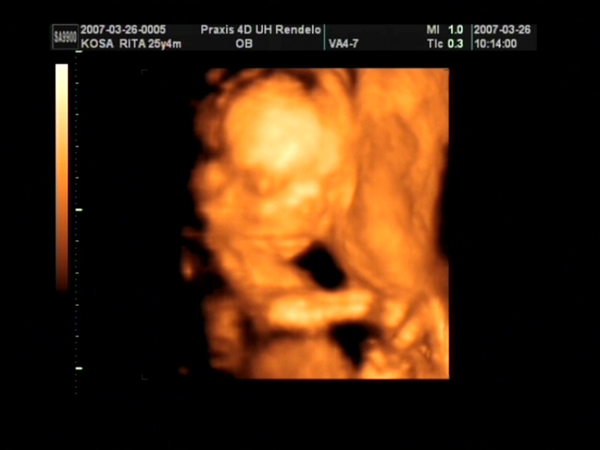

Tegnap voltunk 4D-n. gyönyörű egészséges 31 dekás kislány. :D A Lara Boglárka nevet kapja tőlünk. :) egy kép róla meg egy a pocakról. :)

Kép Kép